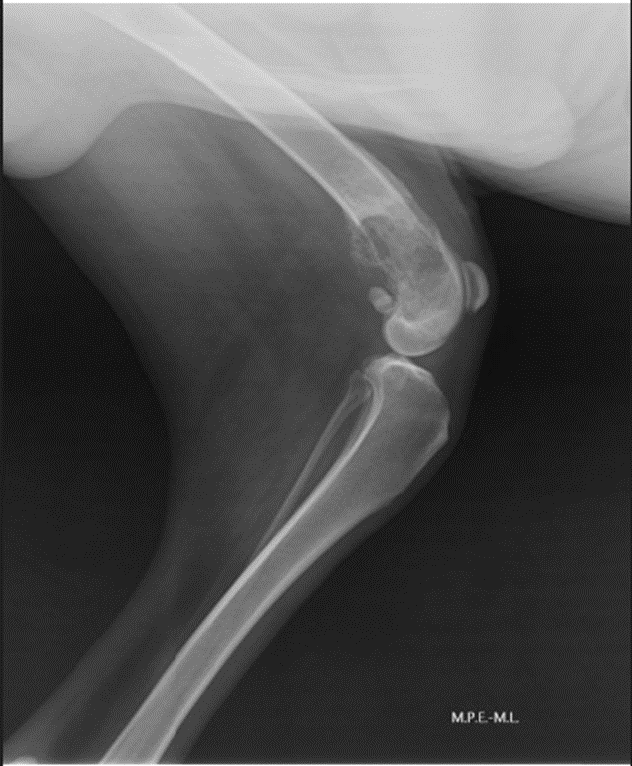

A radiografia de membro, realizada previamente a consulta, revelou lesão osteolítica e proliferativa com reação periosteal irregular, compatível com neoplasia óssea primária. Assim, inicialmente foram realizados exames laboratoriais para estadiamento oncológico e pré-operatórios (hemograma, perfis hepático e renal), ecocardiografia e eletrocardiografia, ultrassonografia abdominal e radiografia torácica, sem alterações relevantes. Após discussão com o setor de cirurgia e com o setor de oncologia, optou-se pela amputação do membro pélvico esquerdo e linfadenectomia inguinal ipsilateral, seguido de análise histopatológica do tumor e do linfonodo inguinal esquerdo. Até o momento da cirurgia, a analgesia foi realizada com tramadol na dose de 2,5 mg/kg e dipirona na dose de 25 mg/kg.

Figura 1: Radiografia do paciente em projeção laterolateral de membro pélvico esquerdo, região de articulação femorotibial, com área de osteólise, em região metafisária de fêmur.